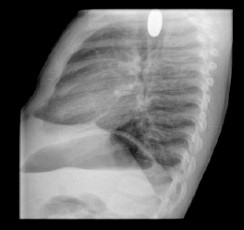

Radiografía de tórax